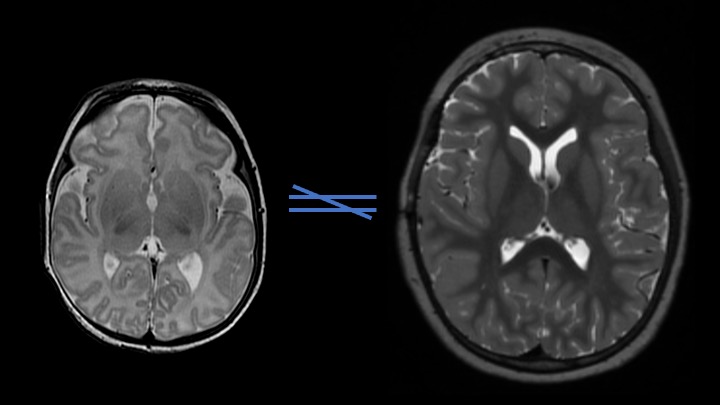

Pediatric autoimmune encephalitis is an immune-mediated, often treatable, cause of encephalopathy and neurologic dysfunction in children. This presentation will cover an overview of the diagnosis, most common auto-antibodies, and associated MRI brain findings.